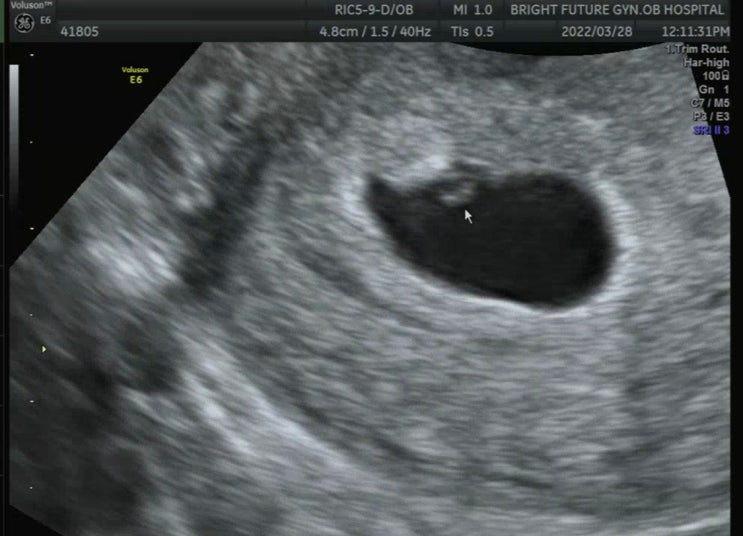

나의 임신 기록 _7 :임신 8주, 10주 초음파 & 주수별 입덧 증상

#임신기록 #임신 #8주차아기집 #임신8주입덧 #임신8주초음파 #임신8주심장소리 #임신8주증상 #임신10주초음...

나의 임신 기록_6 : 임신 6주차 심장소리 & 입덧 지옥..

#임신 #임신기록 #임신6주차 #임신6주3일 #임신6주심장소리 #임신6주초음파 #임신6주입덧 #입덧 #6주차아기...

나의 임신 기록_5 : 임신 5주차 피비침 & 첫 초음파 /병원 선택 :밝은미래 산부인과

#임신 #임신기록 #임신5주차 #임신5주차피비침 #첫초음파시기 #밝은미래산부인과 #입덧 #착상혈 #5주차아기...